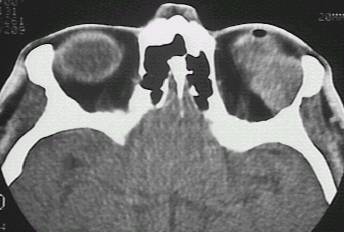

What type of image is it? CT scans or MRI scans (T1 or T2

weighted)

Which plane the image is in? axial, sagittal or coronal.

Describe the image: In ophthalmology, most of the pathology will

be focused on the globe, orbit or the brain. If it were the viva,

ask the examiner for some history.

Examine the following strucutres in order and always compare the

two sides for asymmetry(ies):

globe: eye present (enucleated eye or implant)?

lens present (aphakia)? opacities in the vitreous (blood or foreign body)?

calcification in the retina (retinoblastoma)? calcification in the optic

nerve (drusen)? any abnormal thickening of the sclera (compared with the

opposite eye, thickening suggests scleritis)?

extraocular muscle enlargement (the main differetial

diagnosis include: thyroid eye disease if tendon is not involved or myositis

if the tendon is involved; other possibilities include neoplasm either

primary or secondary)?

space occupying lesion in the orbit: lacrimal

fossa (lacrimal gland tumour)? intraconal lesion (optic glioma, capillary

haemangioma or optic nerve meningioma)? diffuse lesion (lymphoma, metastatic

tumour or acute infection or inflammation)? dilated superior ophthalmic

vein (carotid-cavernous fistula)?

bony lesion: localized bony expansion (meningioma

and osteoma in which the lesions have the same density as the surrounding

bone; fibrous dysplasia in which the bone density is reduced)? any bony

thinning next to an orbital lesion (suggesting long-standing chronic lesion)?

any lytic lesion (suggesting malignant lesions such as metastasis or myeloma)?

brain lesion (enlarged pituiary fossa suggests

pituitary tumour, wedge-shaped hypodense area suggests cerebral ischamia;

wedge-shaped hypodense area suggests cerebral haemorrahge)?